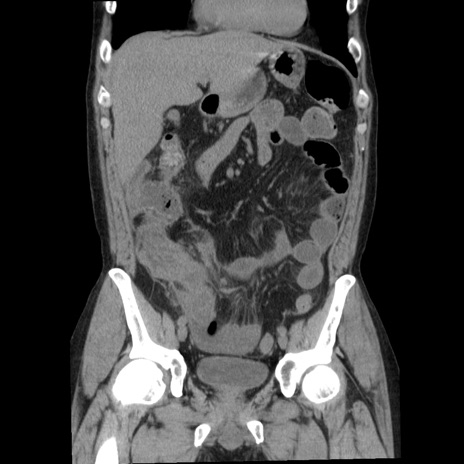

症例29(冠状断像)

【症例】40歳代男性

【現病歴】2日前から胃痛あり。徐々に周期的な激痛に変化した。本日になっても激痛があるため受診。

【身体所見】意識清明、BT 38-39℃台あり、腹部:膨満、やや硬、右下腹部に圧痛あり。

【データ】WBC 8500、CRP 23.26